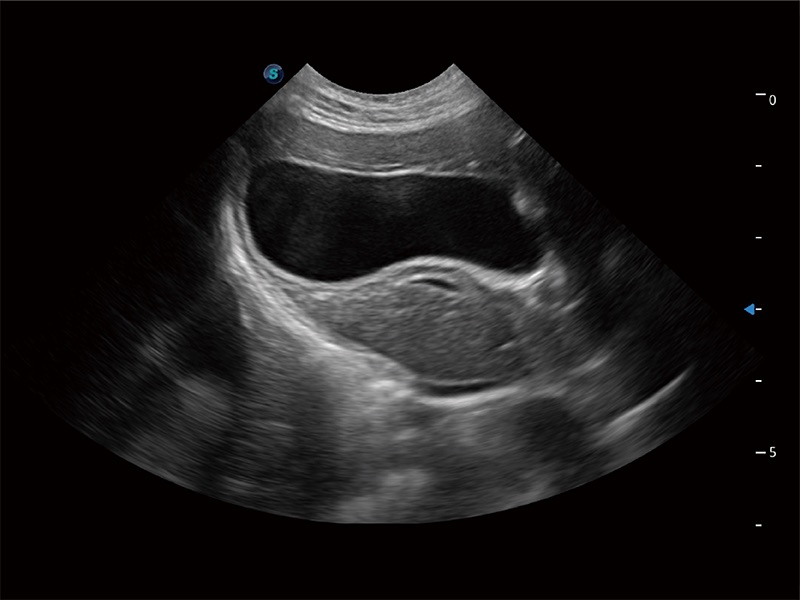

高性能和先进的临床应用工具可以为动物医生提供临床信心。ProPet 80 搭载了先进的腹部和浅表应用工具,帮助医生在日常临床实践中发挥前所未有的作用。

操作简便,无需高频度外力作用即可真实反映组织的形变,快速评估肿瘤良恶性。

ProPet 80 专为动物医生设计,对不同的动物体型和生理结构作出了针对性的优化。通过动物影像专用软件,可满足个性化的应用需求,帮助动物医生获得更精确的诊断数据。

为精细结构及组织边缘提供高清晰度的图像和更大的成像视野。帮助减轻医生的用眼疲劳,快速精准获得测量的数据。